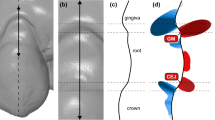

For the gold standard measurements, the adjacent intact teeth and part of the alveolar process were used as superimposition reference area (Fig. 1B). Perfect congruence of the two surface models is expected after a best-fit superimposition of the aforementioned identical surfaces, thus providing optimal spatial relation of the two gingival margins [15,16,17]. The test method measurements were obtained, by using the complete T1 or T2 clinical crowns as superimposition reference (Fig. 1C). An overview of the variables assessed in this study, with the corresponding abbreviations, is presented in Table 1.

Following each superimposition, the depth of the gingival recession was measured as described below. Firstly, a best-fit occlusal plane was defined by manually positioning landmarks on each tooth cusp or at the middle of the incisal edges of the anterior teeth. This step is required for initial automatic placement of the tooth long axis and the unadjusted preformed gingival margin curves by the software. The preformed curves were manually adjusted to each gingival margin (Fig. 2). Following the curve placement, the tooth long axis was definitely oriented by the operator considering all dimensions of space, through visual assessment of the original tooth model from different viewing angles. The axis passed through the center of each tooth that corresponds to the midpoint of the incisal edge for incisors, the center of the cusp for canines, the midpoint of the central groove for premolars, and the central pit for molars. An automated algorithm was afterwards implemented to vertically project each curve onto the user-defined tooth long axis. Along this axis, the most apical point corresponding to each curve was then automatically selected, and the distance between the two subsequent points was registered as the amount of gingival recession (Fig. 3). The orientation of the axis and the tooth center were reset and redefined before each measurement with the different superimposition techniques.

Gingival recession measurement. A Original model. B Recession model and superimposition reference area (blue). C Superimposed models and adjusted curves; colors appear slightly different because of the transparency of the original model. D Tooth long axis placement on the original model. E Overview of gingival margins and tooth axis. F Frontal and lateral view of the adjusted curves and tooth axis configuration; the deepest points of the curves are vertically projected onto the axis (blue lines) and the distance between their projections amounts to the gingival recession